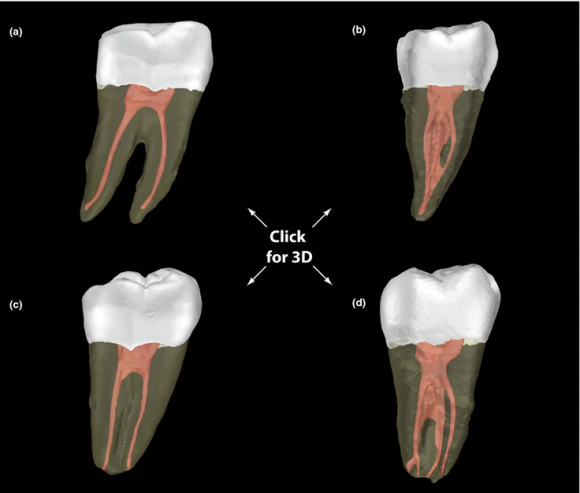

치아 뿌리를 단면으로 잘라보면, (a)처럼 C자 모양의 신경이 치아 내부에서 관찰됩니다.

![[신경치료] 아래 어금니를 신경치료 할 때 치료할 때 알아야 할 것 (C형근관,고난이도치료) 관련 이미지 6](https://pub-9f2bb3498faf4d1d8714b41df24753e3.r2.dev/content/clinics/archive/nqmm0udu86/naver_blog/honeybeevuvu/assets/by_hash/dc3c51c6bcc36524a5c5978c29b1b6e550a7ef293ad3c90e50b5d949eb7b9c30.png)

https://doi.org/10.1111/iej.12256

(a)는 보통의 어금니 신경계, (b)~(d)는 다양한 C형 근관의 해부학적 구조를 보여줍니다.

규칙이랄게 없습니다.

매우 예외가 많고 치료 시 아예 건드려지지 못하는 부분도 꽤 되리라 봅니다.